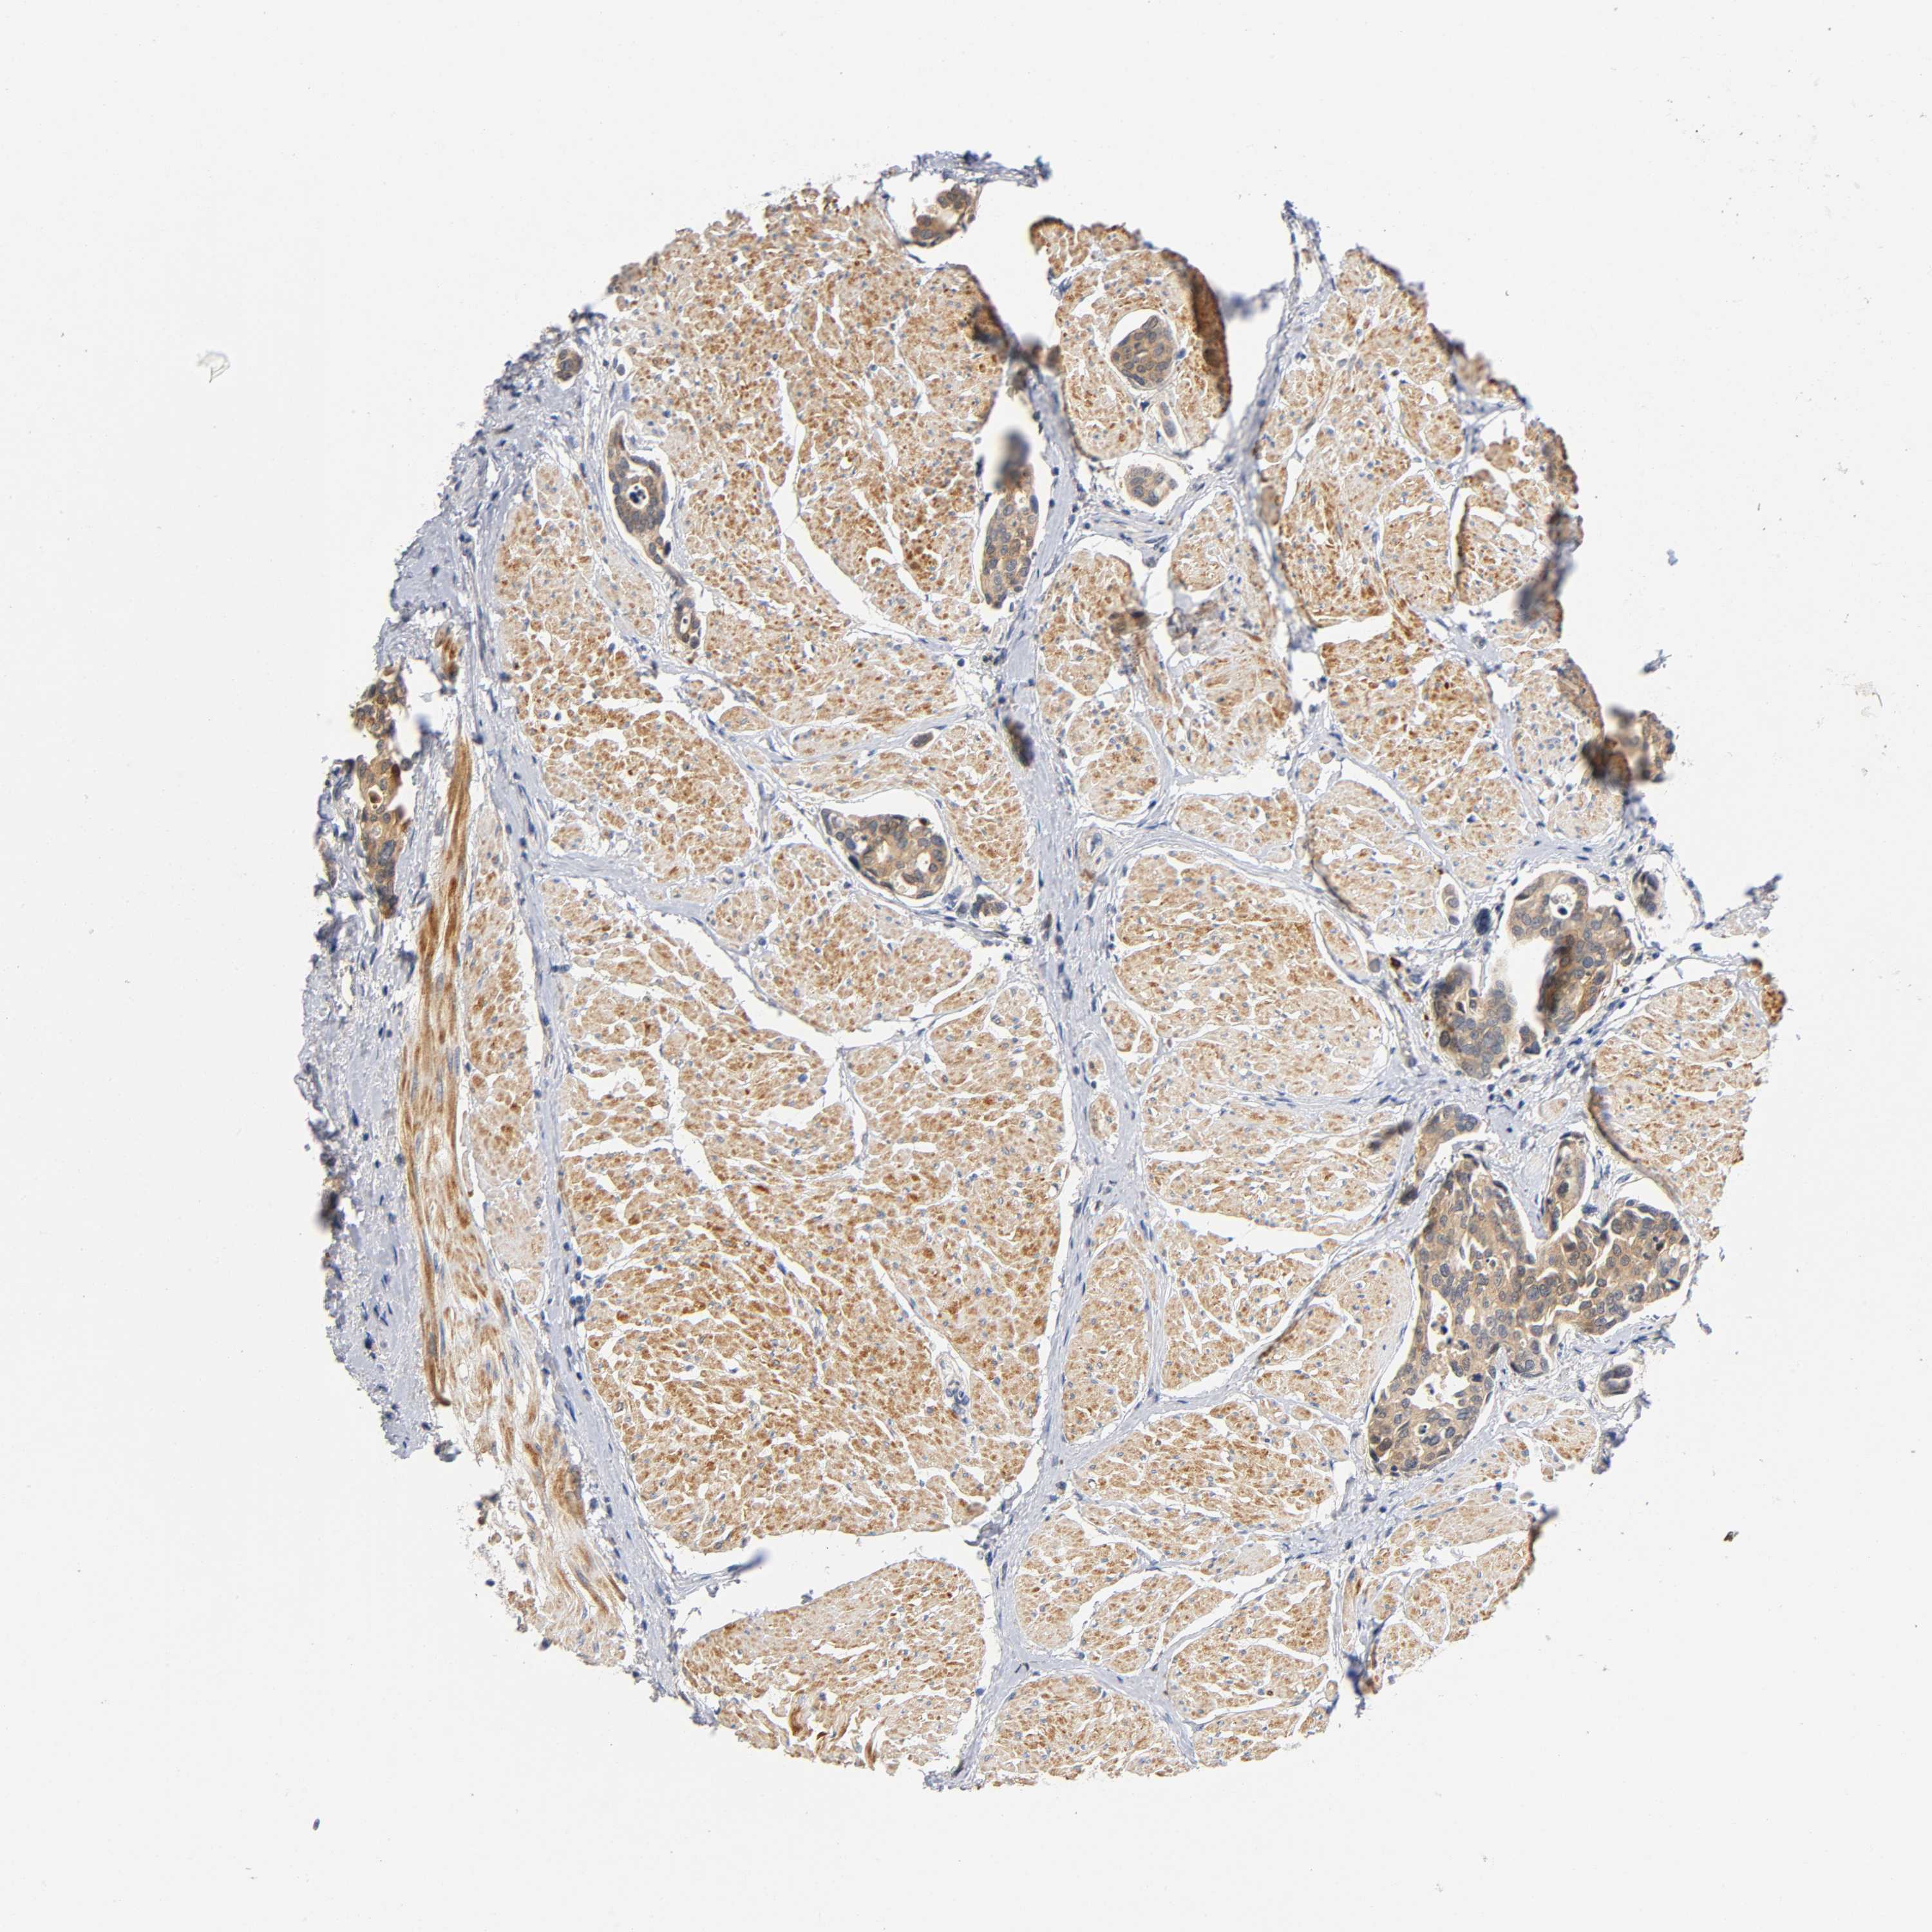

UROTHELIAL CANCER - Protein expressioni

A mouse-over function shows sample information and annotation data. Click on an image to view it in a full screen mode. Samples can be filtered based on level of antibody staining by selecting one or several of the following categories: high, medium, low and not detected. The assay and annotation is described here.

Antibody stainingi

Antibody staining in the annotated cell types in the current human tissue is reported as not detected, low, medium, or high, based on conventional immunohistochemistry profiling in selected tissues. This score is based on the combination of the staining intensity and fraction of stained cells.

Each image is clickable and will lead to virtual microscopy that enables deeper exploration of all samples and also displays staining intensity scores, fraction scores and subcellular localization as well as patient and tissue information for each sample.

Antibody HPA004823

Antibody CAB004592

Staining

High

Medium

Low

Not detected

Intensity

Strong

Moderate

Weak

Negative

Quantity

>75%

75%-25%

<25%

None

Location

Nuclear

Cytoplasmic/membranous

Cytoplasmic/membranous,nuclear

Urothelial carcinoma, Low grade